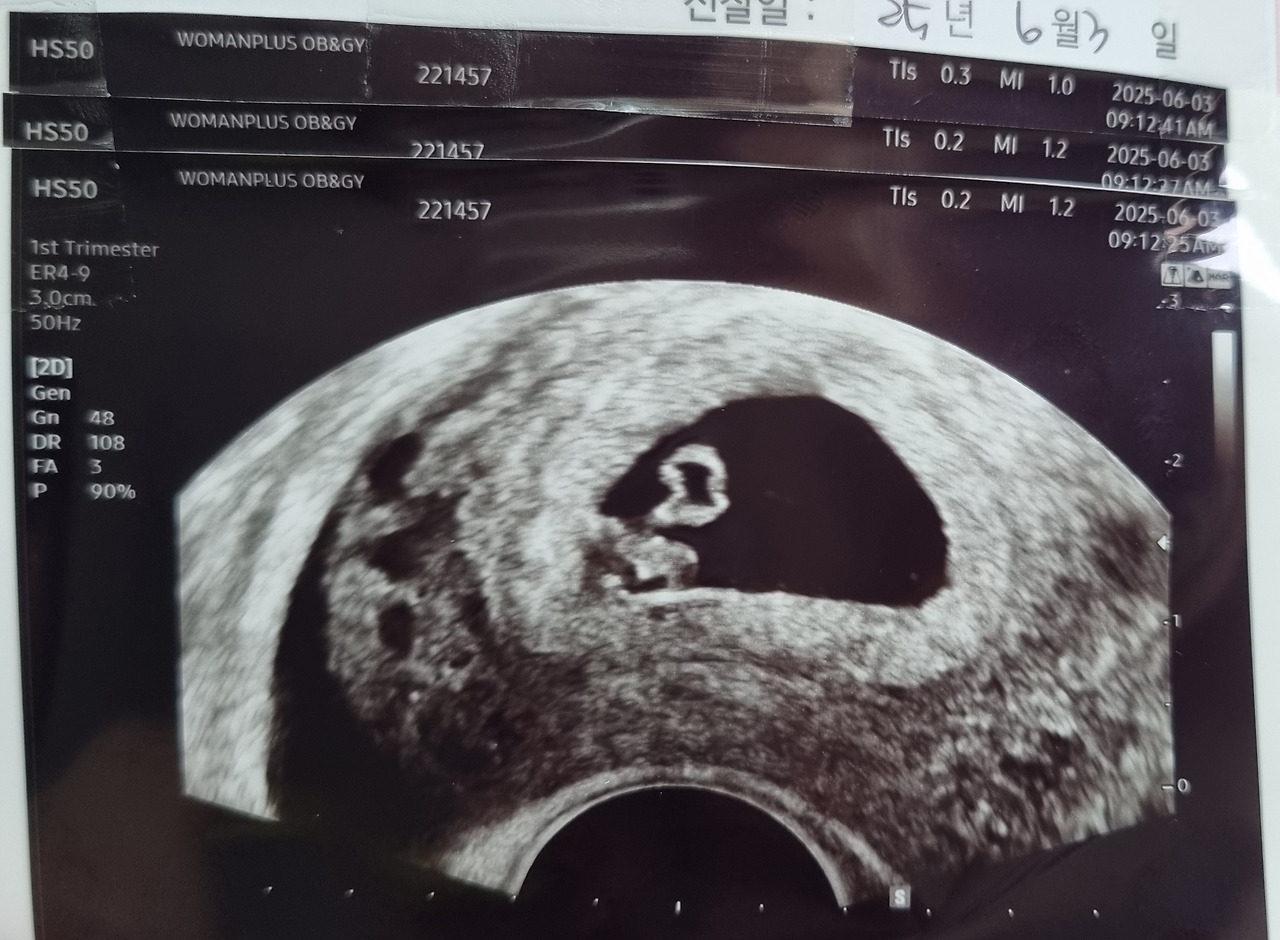

역사적인 날이 왔다

2025.6.3

내 안에 있는 아기를 우리 두 눈으로 확인 한날..!

너무 귀엽게 잘 자라고 있었다니...

주수는 6주 정도 되었다고 하셨다..

저리 작은 생명체 안에 우렁차게 뛰는 심장소리를 들으니 너무도 놀라워서 말을 잇지 못했다..